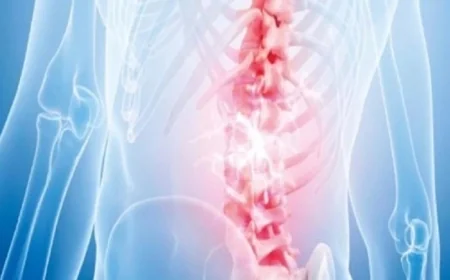

اكتشف طريقة مبتكرة للتخلص من آلام أسفل الظهر المزمنة

اكتشاف علاج جديد لآلام أسفل الظهر المزمنة

توصل الباحثون إلى طريقة مبتكرة وغير تقليدية لعلاج آلام أسفل الظهر المزمنة من خلال استخدام هرمون طبيعي يُعرف باسم “هرمون جار الدرقية”. أظهرت الدراسات أن لهذا الهرمون دوراً في تقوية العظام، بالإضافة إلى قدرته على تقليل الإحساس بالألم بشكل مباشر.

آلية عمل الهرمون

وضحت الدراسة أن “هرمون جار الدرقية” يساهم في منع نمو النهايات العصبية الحساسة داخل الأنسجة المتضررة في العمود الفقري. عند حدوث إصابة، يعمل الهرمون على تشكيل “حاجز وقائي” يمنع الأعصاب المسؤولة عن الألم من دخول المناطق المصابة.

يؤدي هذا التأثير إلى تقليل الإشارات العصبية التي تنقل الألم إلى الدماغ، مما يساهم في تخفيف الشعور بالألم من مصدره بدلاً من مجرد إخفاء الأعراض.

نتائج التجارب

جرى اختبار هذا الهرمون على بعض الحيوانات، حيث أظهرت النتائج أن حقنه أدى إلى تعزيز قوة الأنسجة في العمود الفقري مع حدوث انخفاض ملحوظ في حساسية الألم لدى الحالات التي تم تجربتها.

مقارنة مع العلاجات التقليدية

تعتمد معظم العلاجات الحالية لآلام الظهر على تسكين الأعراض فقط باستخدام المسكنات، دون معالجة السبب الجذري للألم. في المقابل، يستهدف هذا الاكتشاف الجديد السبب البيولوجي المباشر للألم، مما يجعله نهجاً مختلفاً وأكثر تطورًا في مجال العلاج.

إمكانات مستقبلية

يشير الباحثون إلى أن هذا الاكتشاف قد يفتح الأبواب لتطوير أدوية مسكنة حديثة وموجهة، تسهم في تقليل الألم دون الحاجة إلى استخدام مسكنات قوية قد تسبب آثاراً جانبية.